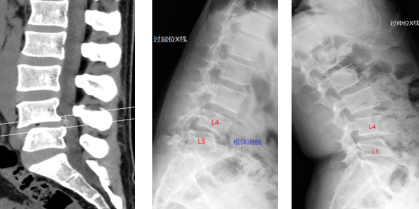

术前讨论会 术前查房

术前影像学检查提示:腰4/5椎管狭窄,腰4椎体前滑脱I°。

术后X线、CT提示:腰椎内固定螺钉位置良好,腰椎滑脱复位满意。